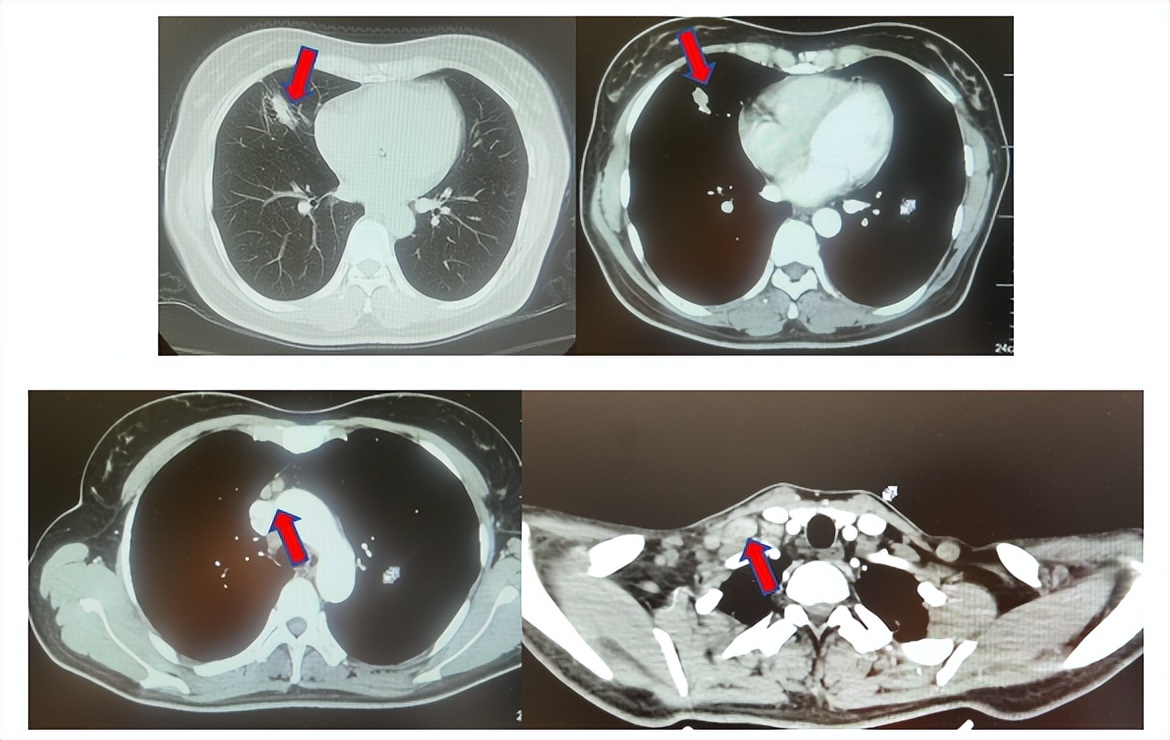

患者符合我科正在开展的一项“评估信迪利单抗或安慰剂联合培美曲塞和铂类化疗用于晚期或复发性肺鳞状细胞非小细胞肺癌一线治疗有效性和安全性的随机,双盲,III期研究(ORIENT-11)”临床研究入组条件,应用信迪利单抗或安慰剂联合培美曲塞+卡铂治疗4周期,信迪利单抗或安慰剂联合培美曲塞维持治疗13周期,后应用信迪利单抗或安慰剂应用至2年。试验结束后出组,揭盲患者为信迪利治疗组。治疗期间最佳疗效肺内病灶近CR(图6)。停药后每3个月-6个月复查随访,未见肿瘤复发转移征象(图6),截止至目前为止,一线无进展生存已超过75个月。

图6:上三图分别展示2019年6月患者达到最佳疗效时肺CT肺窗及纵隔窗右肺中叶病灶及锁骨上淋巴结影像,下两图表示2025年2月患者最近复查评效时肺CT肺窗及纵隔窗肺内病灶影像